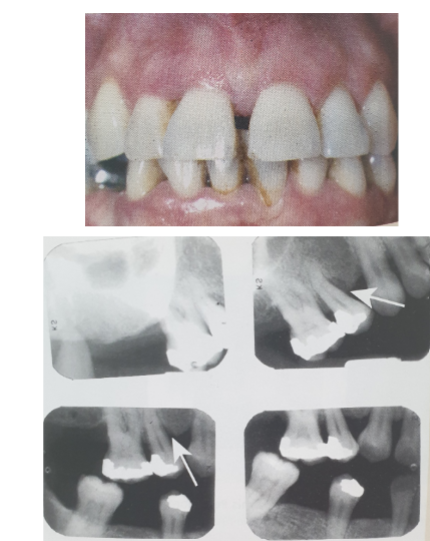

16

Q

How else beside measurement, can we calc PD? Give percentage and classifications for it:

A

xrays

sub gingival calculus

last pic is stage 3-4

17

Describe stage

loss of lamina dura

duzzy

black triangles

flat line bone loss = cloudy look

18

Stage 2 x-ray PD looks like…